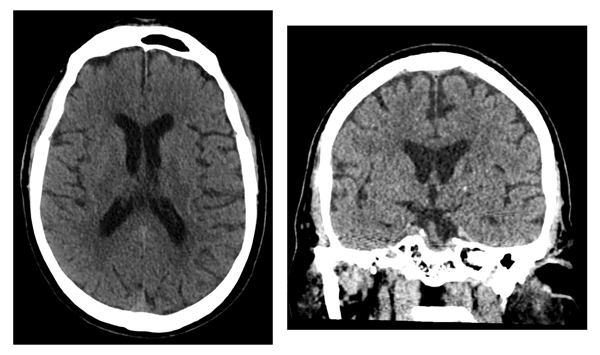

In the emergency department (ED), non-contrast head CTs are routinely acquired for patients with neurologic symptoms. Anecdotally, non-contrast head CTs performed in patients with prior negative findings on CTs performed for the same clinical indication are of low diagnostic yield. As such, a team of scientists led by the UC San Francisco Department of Radiology and Biomedical Imaging's Neuroradiology Section evaluated the rate of findings in patients who received serial head CTs in the emergency department. They hypothesized that the rate of acute findings in non-contrast head CTs performed in patients with a preceding negative study performed for a similar indication would be lower compared with patients being imaged for the first time or for a new indication. Findings were recently published in the American Journal of Neuroradiology (AJNR).

To perform the research, scientists retrospectively analyzed approximately 10,000 CT scans performed in the ED setting over a four-year period. Scans show that a prior negative CT performed for a similar indication makes it much less likely that a new CT will have a clinically significant finding when compared to first-time examinations or examinations performed for a new indication. Results suggest that a prior negative head CT examination has a negative predictive value in terms of the likelihood that a new exam performed for the same clinical indication will be positive.